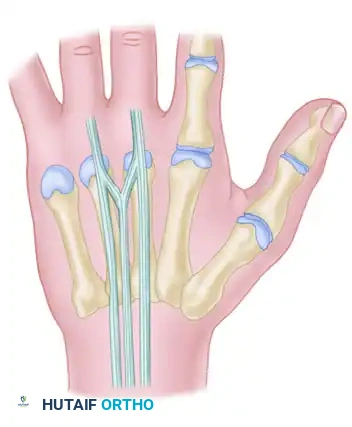

FIGURE 66-62: Most common pattern of extensor tendons on the dorsum of the hand, illustrating the single EIP, single EDC to index and long fingers, double EDC to the ring finger, absent EDC to the small finger, and double EDQ.

Extensor indicis proprius (EIP) anatomy, demonstrating its classic ulnar relationship to the EDC of the index finger.

Additional anatomical variations and interconnections of the dorsal extensor mechanism are illustrated below, highlighting the complexity surgeons must navigate during dorsal hand reconstruction:

Surgical diagram illustrating the trajectory of tendon repair and the complex interplay of the dorsal apparatus during fixation.